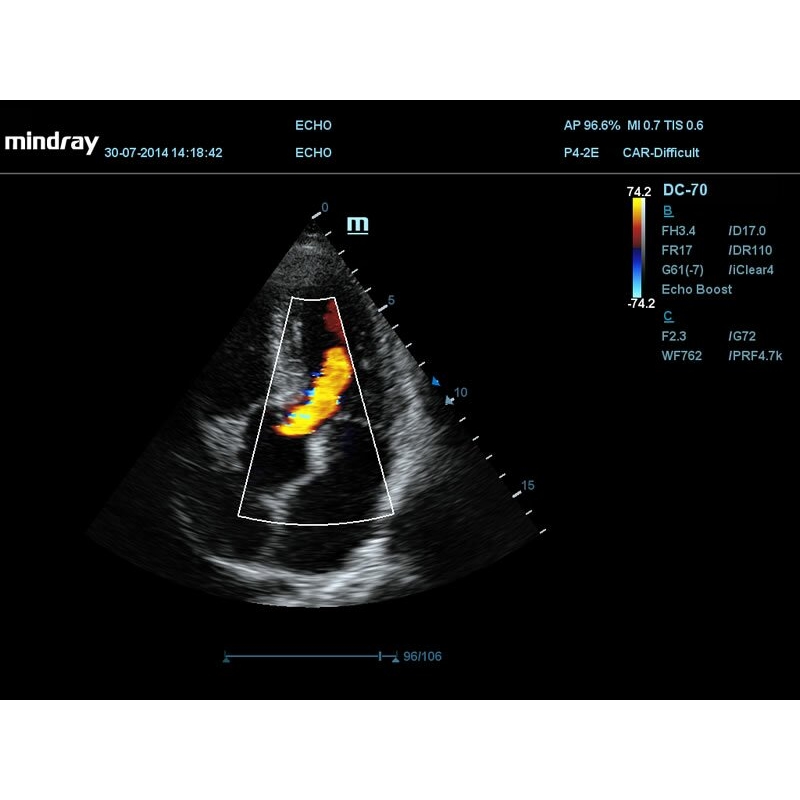

- Опция для проведения обследования с применением контрастных веществ (поддерживается на датчиках SC6-1E, C5-1E, C5-2E, L12-3E, L14-5WE, L9-3E, V11-3E, V11-3HE, DE11-3E);

- Пакет для количественного анализа при проведении обследований с применением контрастных веществ (необходима опция UWN Contrast Imaging);

- Пакет программ для исследования левого желудочка с контрастированием (доступен на датчиках SP5-1E, P4-2E).